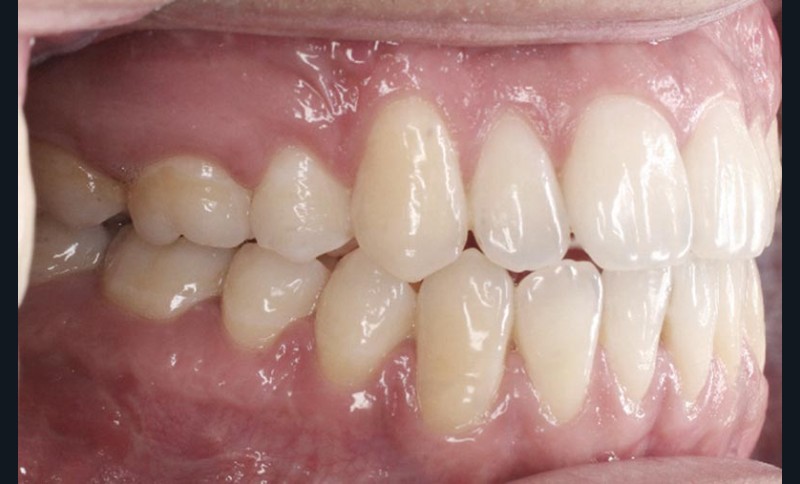

Les résultats esthétiques et occlusaux satisfont amplement le patient qui revient pour un contrôle à long terme 10 ans après l’intervention montrant la stabilité des résultats.